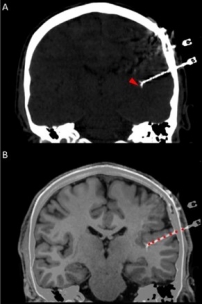

In addition to the very valuable iEEG recordings from the clinical macroelectrodes, our iEEG recordings also include signals recorded with microelectrodes. The additional microelectrodes have a diameter of about 40 μm (smaller than the hair) and spread out of the tip of the clinical intracranial electrode. They are added solely for research purposes and, because of their small size, they can record the electrophysiological firing activity generated by nearby individual neurons. We analyze this data by using algorithms which classify the different waveforms recorded by a single microwire into action potentials generated by different neurons. We also use population decoding methods to extract the information associated by the neurons (e.g. “concept” neurons which preferably fire in response to specific images of the same individual). To localize the site of the macro- and micro-electrodes with high spatial resolution, we combine post-implantation CT scans with pre-implantation neuroimaging scans from the 7-Tesla MRI, available at the University of Magdeburg.

1. © Grande et al. 2020. The image is a cropped version of the original. Reproduced according to the terms of Creative Commons Attribution License. Grande, Krista M., Sarah K. Z. Ihnen, and Ravindra Arya. 2020. “Electrical Stimulation Mapping of Brain Function: A Comparison of Subdural Electrodes and Stereo-EEG.” Frontiers in Human Neuroscience 14 (December). https://doi.org/10.3389/fnhum.2020.611291.

2. © Greene et al., 2021. Reproduced according to the terms of Creative Commons Attribution License. Greene, Patrick, Adam Li, Jorge González-Martínez, and Sridevi V. Sarma. 2021. “Classification of Stereo-EEG Contacts in White Matter vs. Gray Matter Using Recorded Activity.” Frontiers in Neurology 11 (January). https://doi.org/10.3389/fneur.2020.605696.